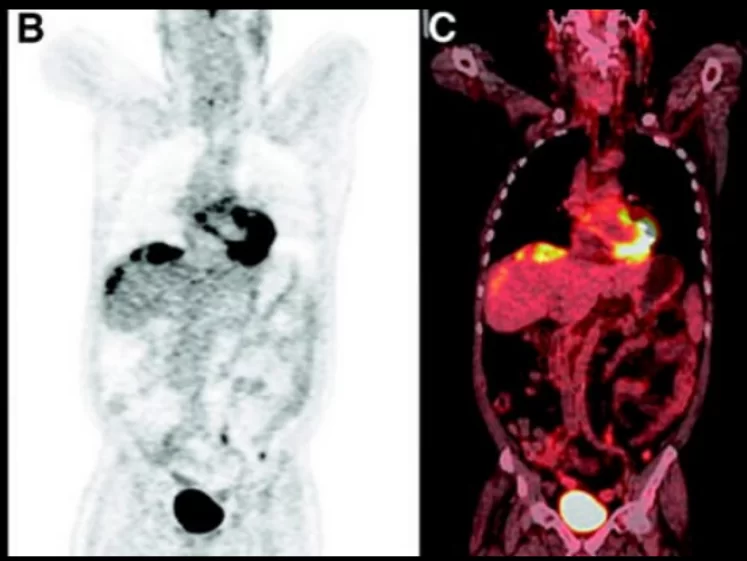

O PET-CT Oncológico com Thyrogen® é uma técnica avançada de imagem que combina a tomografia por emissão de pósitrons (PET) com a tomografia computadorizada (CT) para avaliar o câncer, utilizando Thyrogen® para otimizar a detecção de câncer da tireoide. Este exame é particularmente útil para pacientes que foram submetidos a tratamento para câncer de tireoide e precisam de monitoramento contínuo.

O PET-CT Oncológico com Thyrogen® combina duas tecnologias poderosas para uma avaliação detalhada do câncer. O PET detecta a atividade metabólica das células cancerosas através do uso de um traçador radioativo, enquanto o CT fornece imagens anatômicas detalhadas. Thyrogen® é um medicamento utilizado para estimular a produção de hormônio tireoidiano e melhorar a captação do traçador radioativo, especialmente útil para detectar recidivas de câncer de tireoide.

- Tomografia por Emissão de Pósitrons (PET): O paciente é posicionado em uma máquina PET que detecta a radiação emitida pelo FDG. As imagens PET mostram a atividade metabólica das células tumorais.

- Tomografia Computadorizada (CT): Imagens CT são obtidas para fornecer uma visão anatômica detalhada, que é combinada com as imagens PET para uma avaliação completa.

- Análise dos Resultados: As imagens PET-CT são analisadas por um radiologista especializado, que interpreta a distribuição do FDG e identifica áreas de interesse.